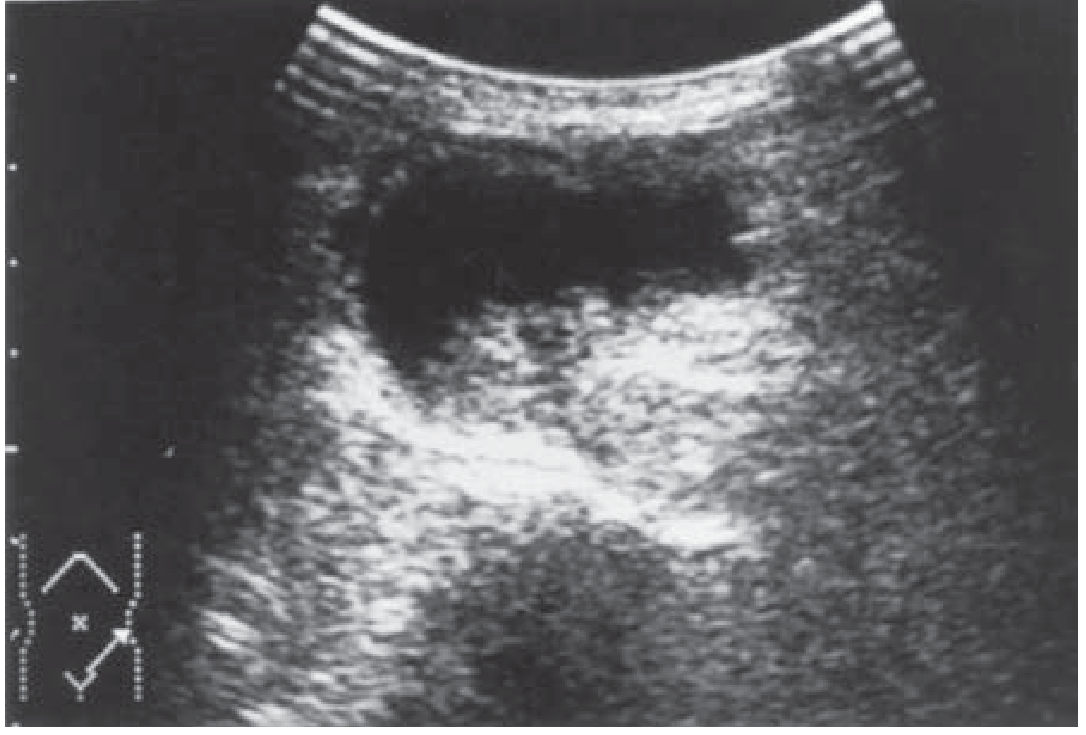

| Bowel loop in inguinal canal | Hernia (bowel hernia) |

| Echogenic fat in canal | Omental/fatty hernia |

| Posterior acoustic shadowing | Air in bowel lumen |